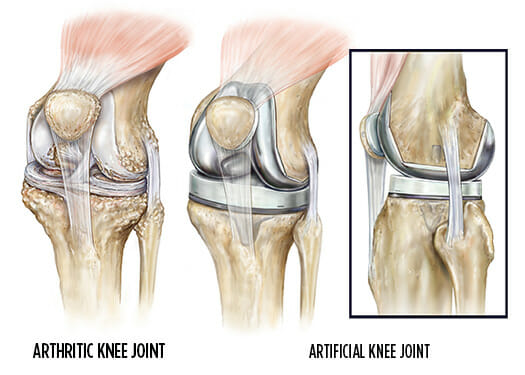

Total Knee Replacement (TKR), also known as knee arthroplasty, is a surgical procedure that replaces the entire knee joint with an artificial prosthesis to relieve pain and improve function. This procedure is typically recommended for individuals suffering from severe knee pain and limited mobility due to conditions such as osteoarthritis, rheumatoid arthritis or traumatic injury.

Resurfacing : Damaged bone and cartilage are removed from the femur, tibia and patella. Metal components are then attached to the ends of these bones and a plastic spacer is placed in between them to create a smooth surface for movement.